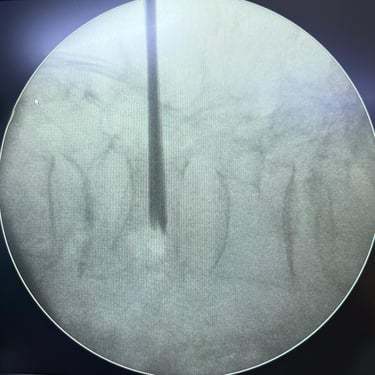

Fractura Lumbar Osteoporótica / Vertebroplastía y Bloqueo Lumbar Selectivo

La fractura lumbar osteoporótica y la artrosis lumbar son causas frecuentes de dolor crónico y limitación funcional en el adulto mayor. La osteoporosis debilita las vértebras, favoreciendo fracturas incluso ante esfuerzos mínimos, mientras que la artrosis genera desgaste articular e inflamación. La vertebroplastía percutánea permite estabilizar las vértebras fracturadas mediante la inyección de cemento óseo, proporcionando alivio rápido y mejorando la movilidad. En casos de dolor persistente por artrosis, el bloqueo lumbar selectivo ayuda a reducir la inflamación y el dolor. Ambas técnicas son procedimientos mínimamente invasivos que mejoran la calidad de vida y facilitan la recuperación funcional.